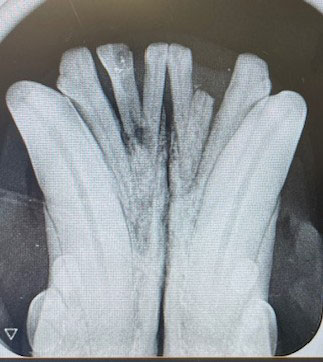

Dentalröntgen – der Goldstandard

• Digitale Zahnradiografie aller Zähne

• Beurteilung von Wurzelresorption, FORL, Abszessen und Frakturen

• Diagnose auch bei äußerlich unauffälligen Zähnen